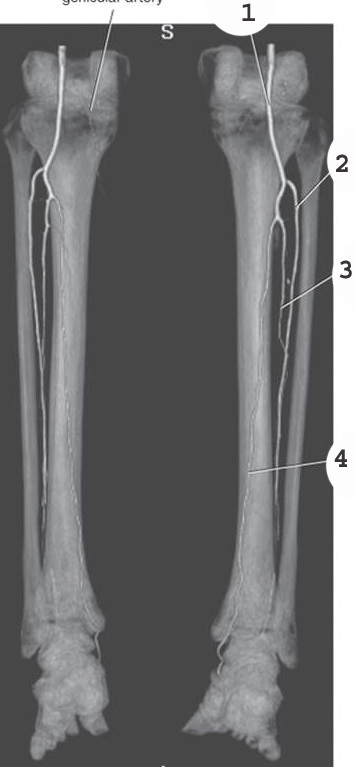

1

popliteal artery